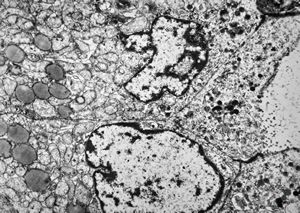

F, 71y. | carcinoid … metastasis to lymphonode